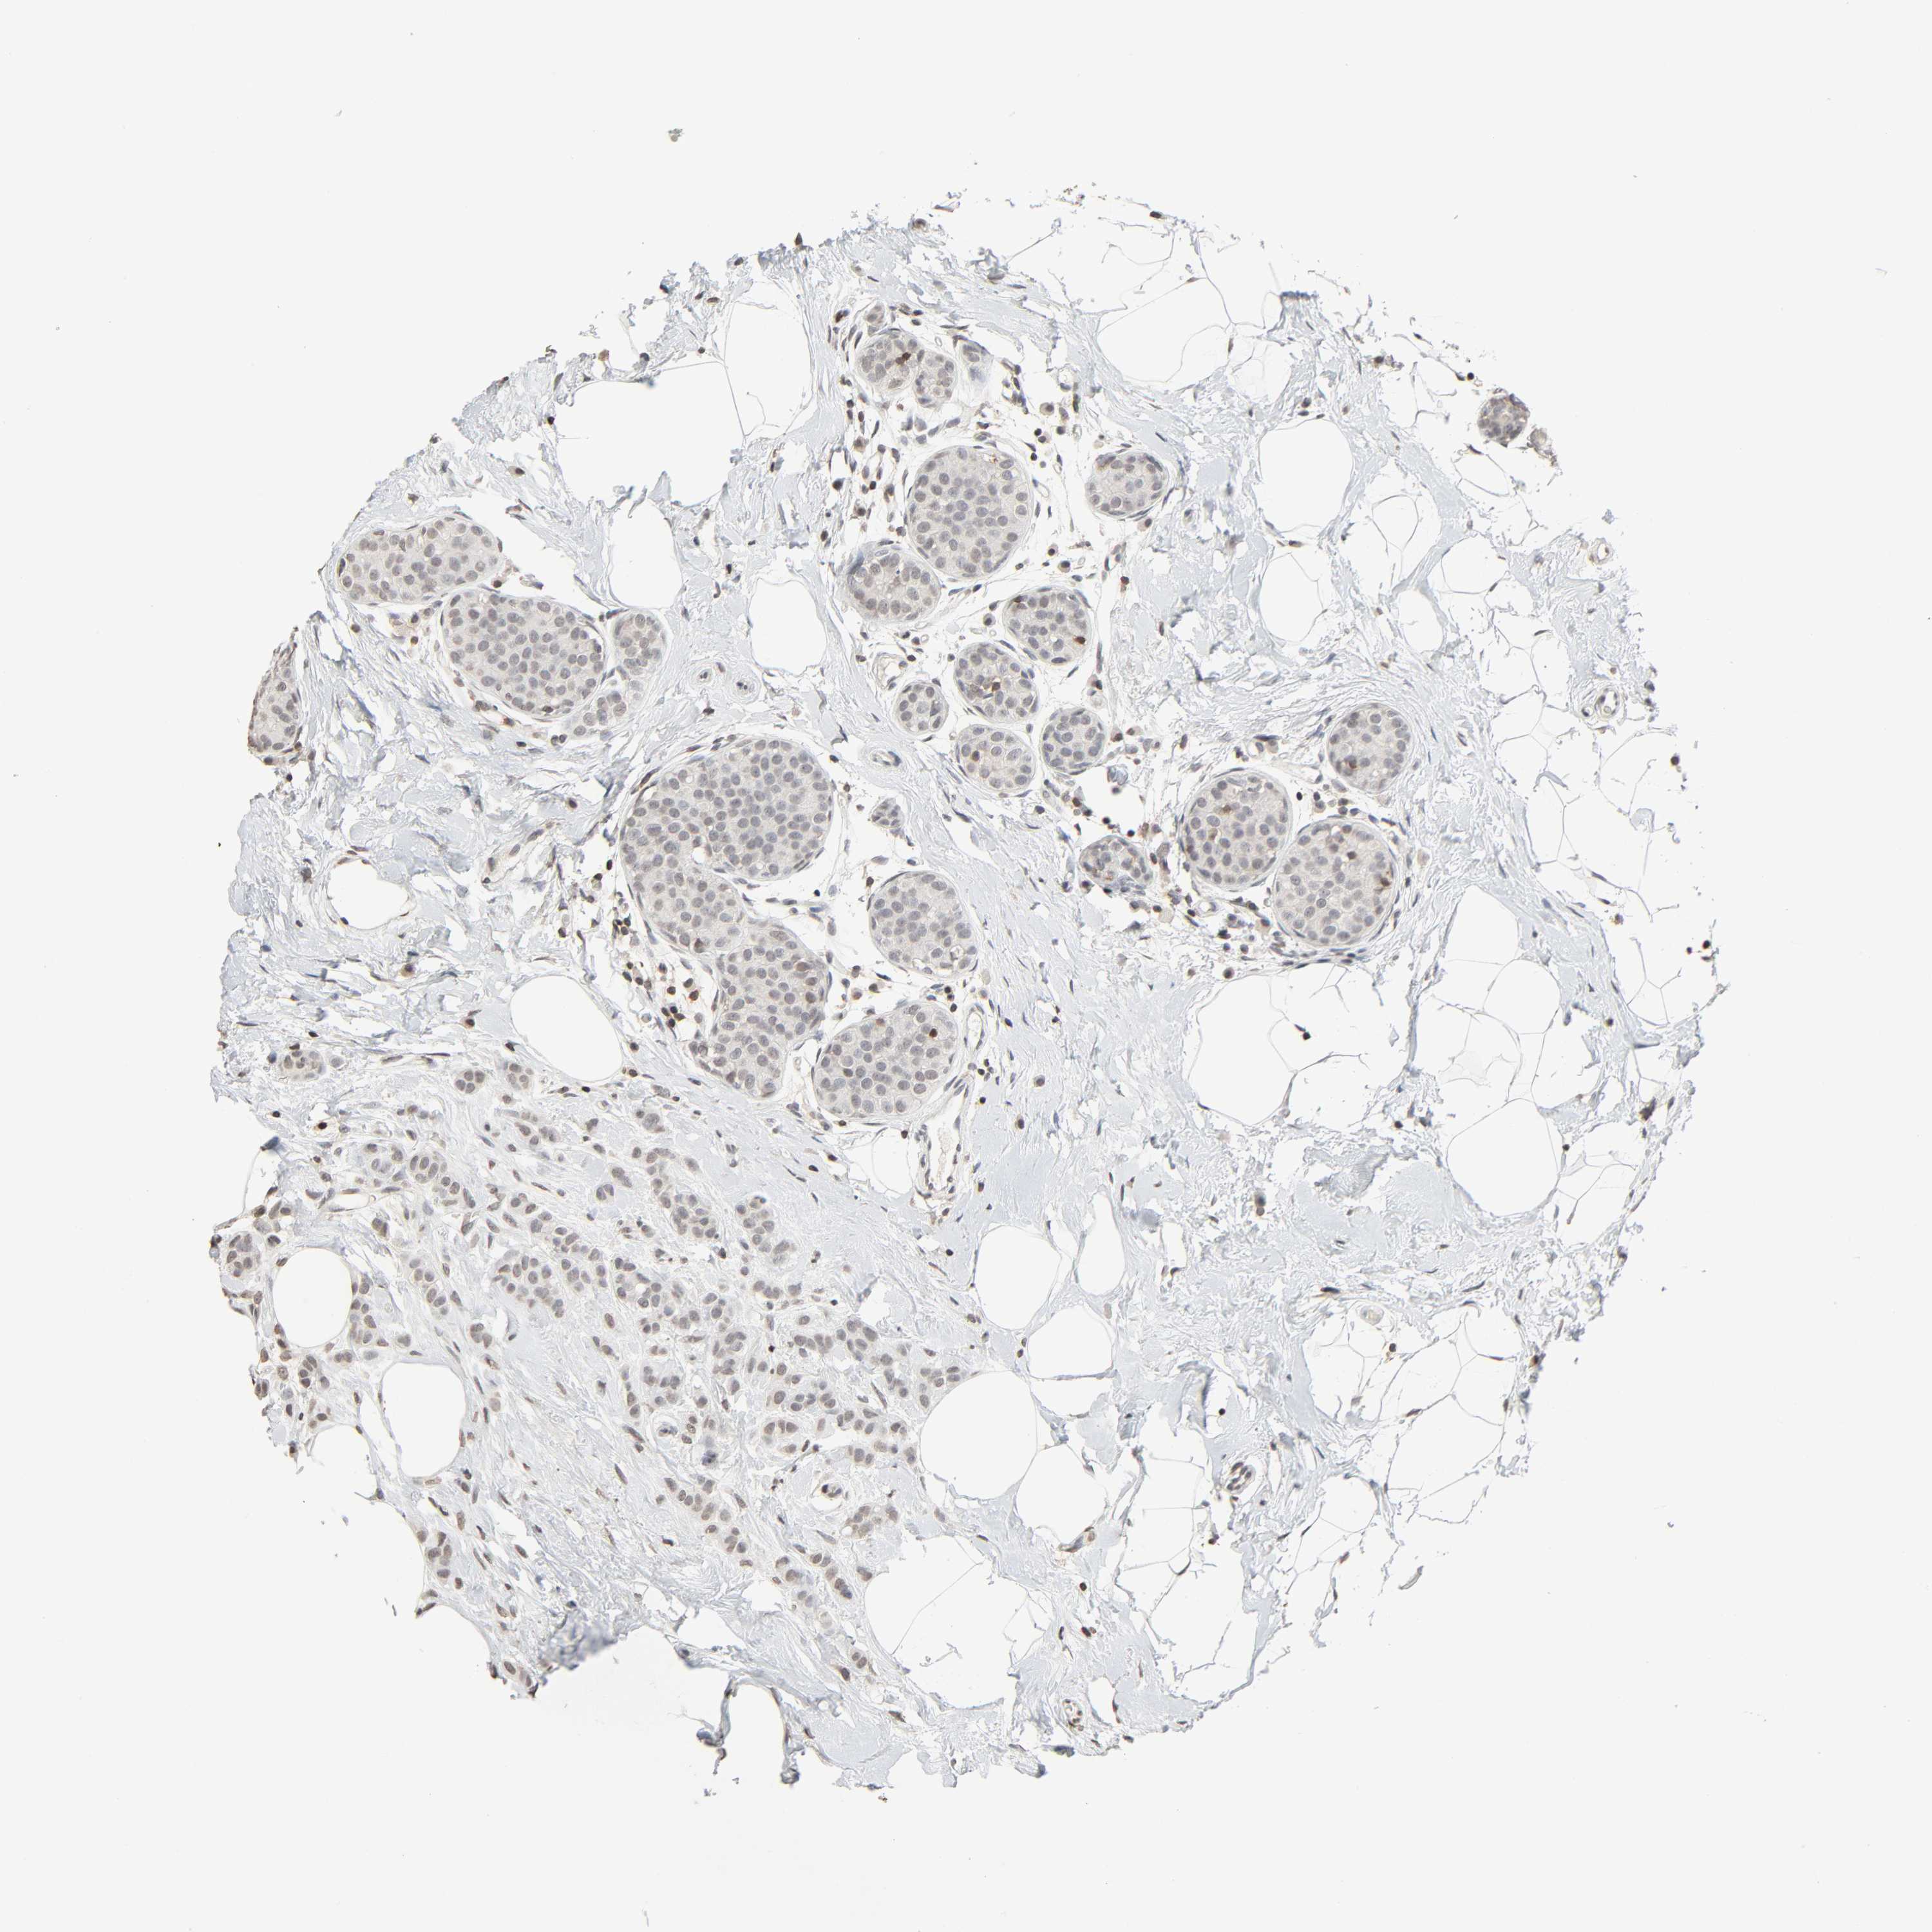

BRCA TCGA BRCA VALIDATION PROTEIN EXPRESSION